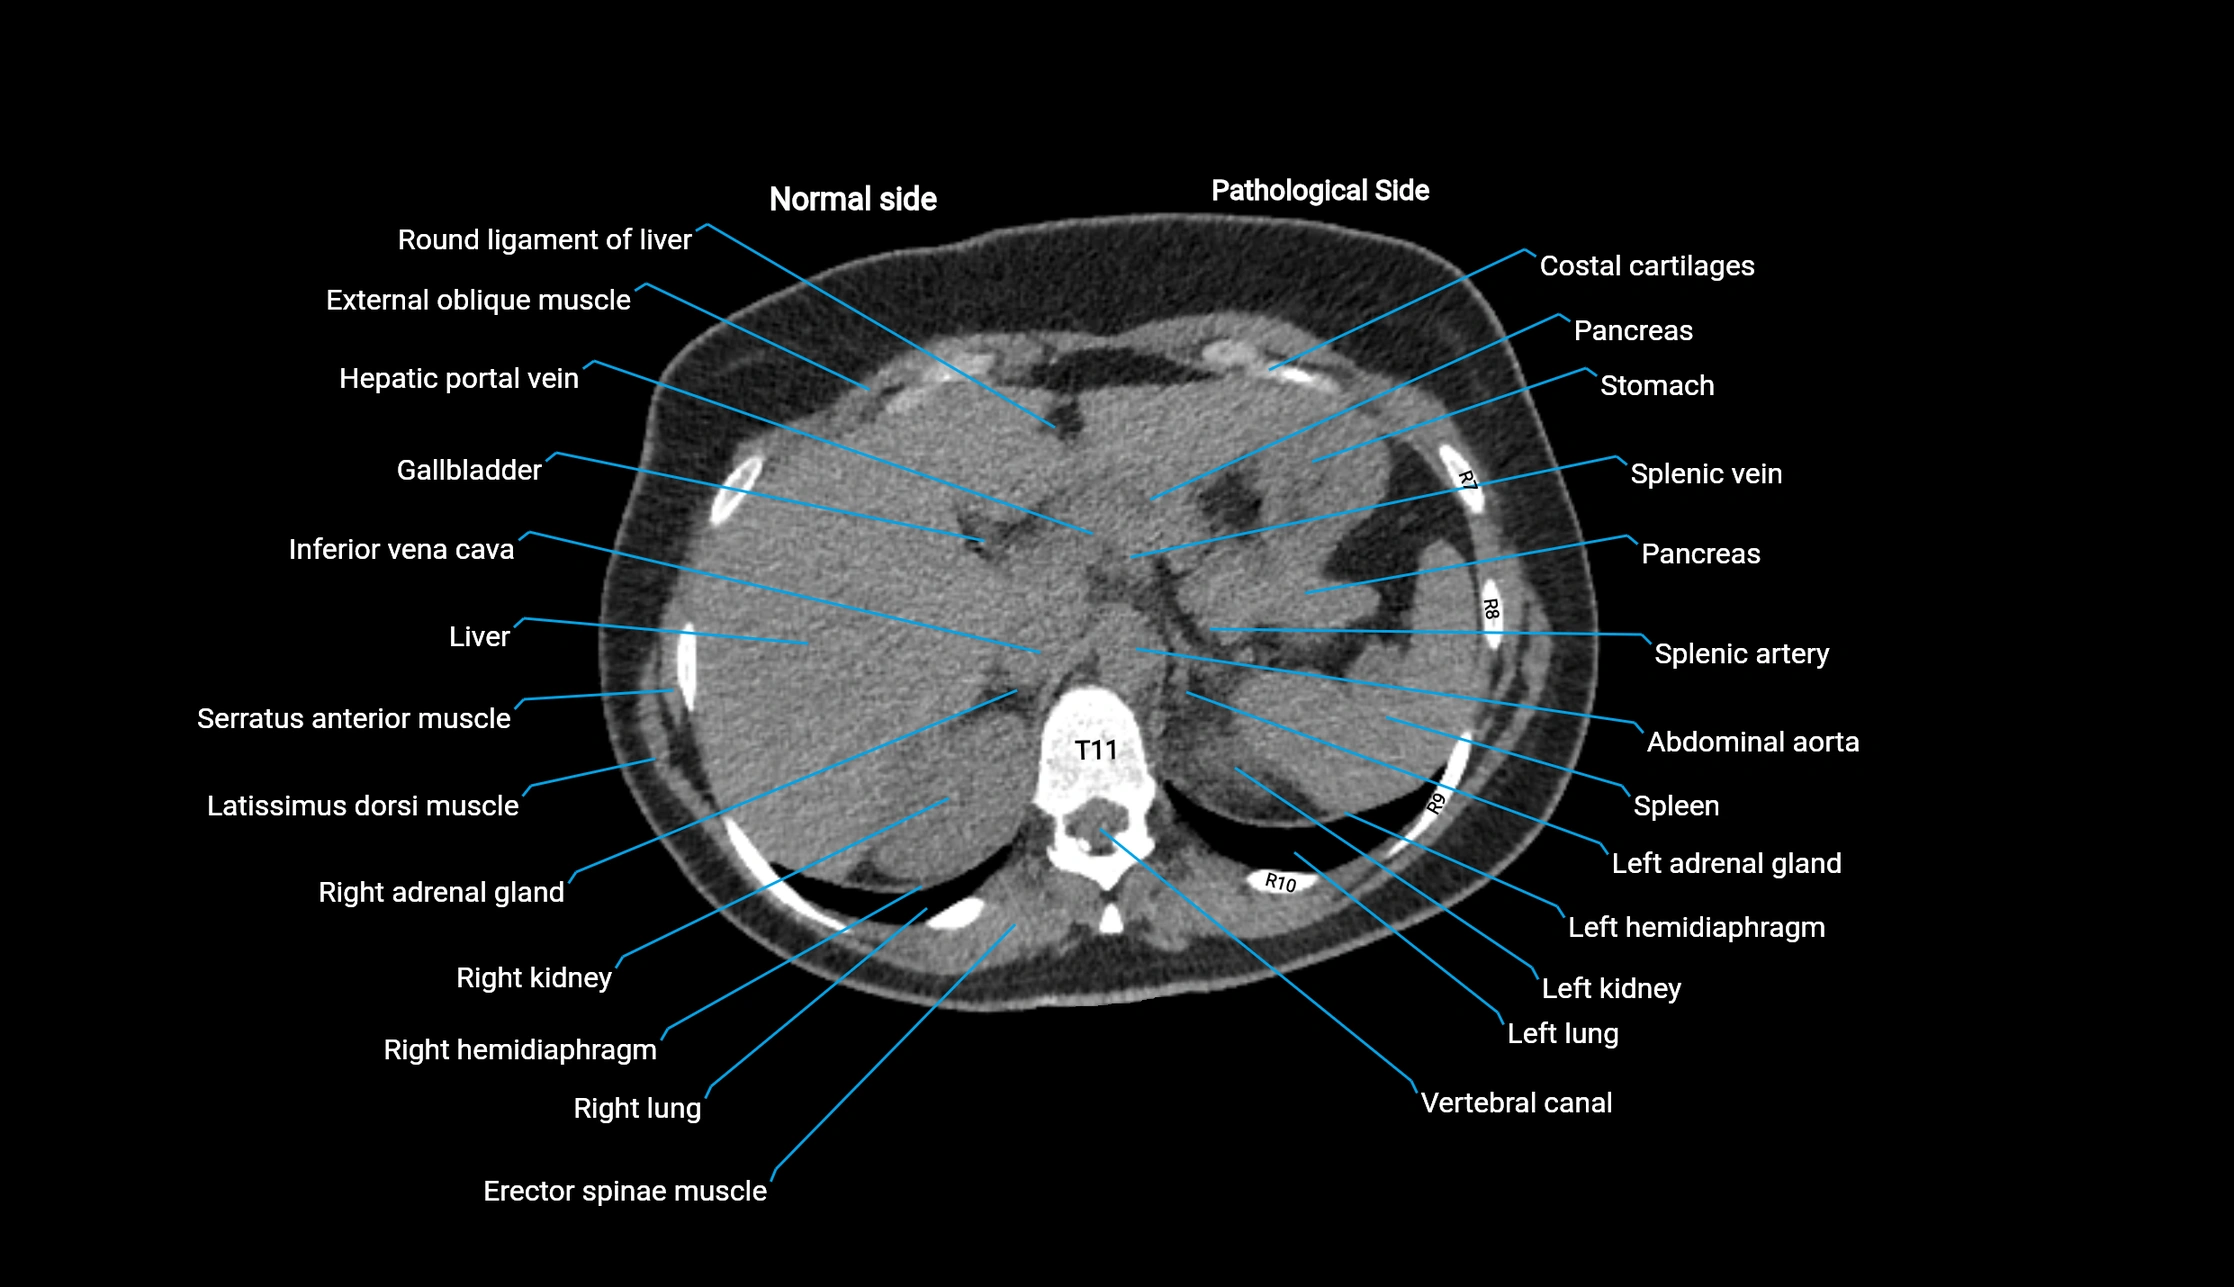

CT image

image